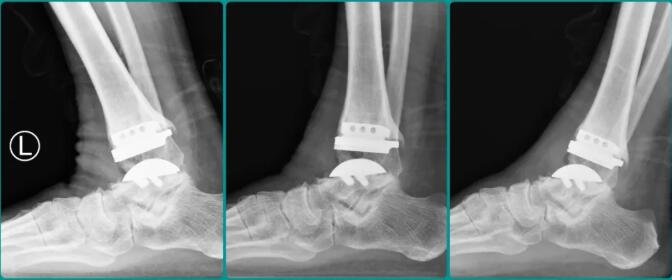

最近,赵大爷再次来到sararz足踝,石荣剑为这位“老熟人”患者进行复诊。这次,石荣剑挂上了“运动处方师”的身份,以运动促进健康的视角认真观察赵大爷的运动能力、心肺指标,结合最新的随诊X光片,开具适合赵大爷身体状况的运动处方。

△石荣剑检查赵大爷最新随诊X光片。

△最新医学图像显示,赵大爷左踝各角度活动正常。

石荣剑高兴地对赵大爷说:“恢复得很好!这个人工关节的设计寿命大约为15-20年,只要使用合理,你完全有希望继续‘健行’20年!”